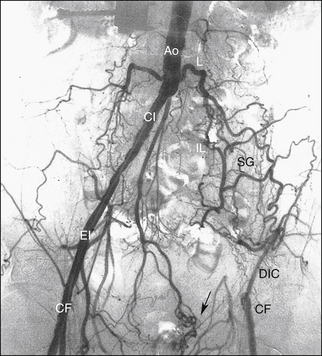

РИСУНОК 13-9. А. Брюшная аорта (Ао) заканчивается разветвлением на общие подвздошные артерии (CI) на уровне позвонка L4. Б. Общие подвздошные артерии делятся в пояснично-крестцовом соединении на внутреннюю (II) и наружную подвздошную (EI) артерии. Внутренняя подвздошная артерия (также называемая подчревной артерией) снабжает внутренние органы и мускулатуру таза. Ветви этой артерии становятся важными сопутствующими путями, как видно на других рисунках. Наружная подвздошная артерия переходит в общую бедренную артерию у паховой связки, как показано на рисунке 13-10 . C : Трехмерная объемная (VR) компьютерная томографическая (КТ) ангиограмма аорты и сегмента подвздошно-бедренной артерии. D. Проекция максимальной интенсивности (MIP) КТ-ангиограммы подвздошно-бедренных сегментов демонстрирует очаговые кальцификации в открытых сосудах. E — магнитно-резонансная ангиограмма (МРА) с усилением гадолинием аорты, подвздошного и бедренного сегментов. Анатомия наглядно иллюстрируется методами трехмерной реконструкции. С, чревная артерия; H, печеночная артерия; НМА, нижняя брыжеечная артерия; R, левая почечная артерия; рРГ – замена правой печеночной артерии; S, селезеночная артерия; СМА, верхняя брыжеечная артерия.